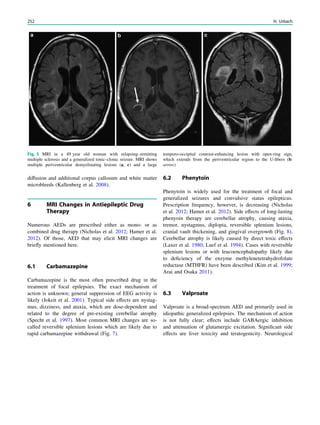

Fig. 2 Dural a. v. fistula. A 53-year-old man presented with two tonic–

clonic seizures. MRI shows circumscribed edema in the left frontal lobe

(a, hollow arrow) and an abnormal vessel running in the left sulcus

rectus (c, arrow). The digital subtraction angiogram of the left internal

carotid artery shows a frontobasal dural arteriovenous fistula fed via

ethmoidal arteries (d, arrow) and confirms the abnormal vessel as a

draining vein (e, arrow)